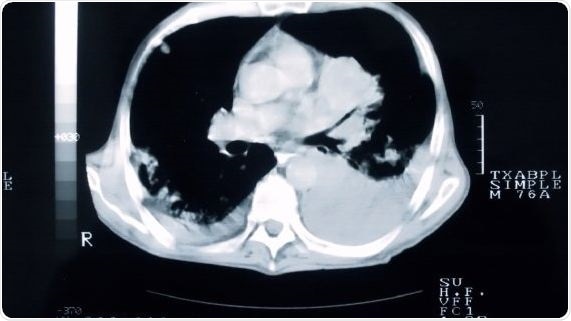

The findings of the study, looking at the effect of CT screening on smokers at high-risk of developing lung cancer, dispute the belief that a negative screening result offers a ‘license to smoke’ and reveal that engaging with lung screening can give smokers an opportunity to access smoking cessation support, at a time when they are likely to be receptive to offers of help.

The trial, led by researchers at Cardiff University working with the University of Liverpool, King’s College London and Queen Mary University, involved 4,055 participants aged 50-75 years who were randomized either to a group who underwent low-dose CT screening for early detection of lung cancer, or to a control group who did not undergo screening.

Of the smokers who took part in the screening, 10% had successfully quit after two weeks, and 15% had quit at two years – both higher than rates in the control group.

The UK Lung Cancer Screening (UKLS) pilot trial is the first to assess the feasibility, cost-effectiveness and behavioral impact of lung cancer screening, using a single low-dose CT screen on a high-risk population in the UK.